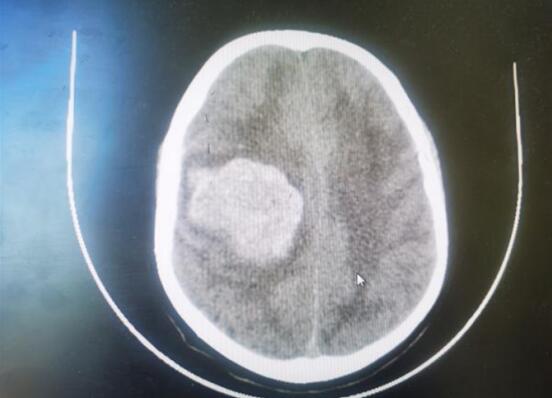

近日,一例56歲大量腦出血的中年患者,在江寧中醫(yī)院得到成功救治。患者突發(fā)暈倒,急查頭顱CT顯示:顱內(nèi)出血約70ml,既往有口服“阿司匹林”用藥史,神經(jīng)外科醫(yī)生在權(quán)衡利弊后,決定予以開顱血腫清除+去骨瓣減壓術(shù)。醫(yī)生們與死神賽跑,經(jīng)過4個小時的手術(shù),術(shù)后第二天患者蘇醒。

術(shù)前CT